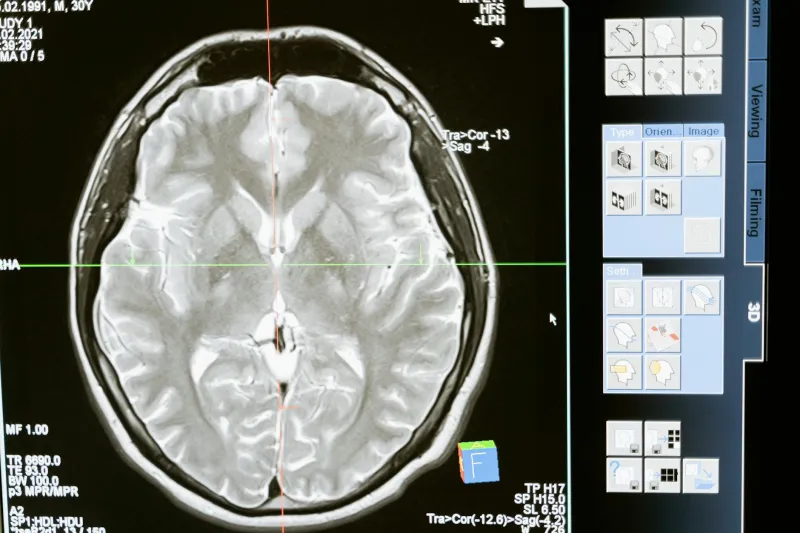

What Brain Scans Actually Show

Modern brain imaging technology — from PET scans to functional MRIs — reveals something remarkable about human brain activity. Even during simple tasks like reading this sentence, multiple regions across your brain light up simultaneously. When you're "just" sitting quietly, your brain is still humming with activity in what scientists call the "default mode network."